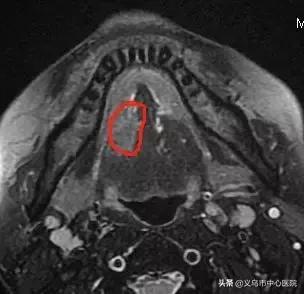

“我们马上为病人量身定制了一套治疗方法。”中心医院口腔颌面外科主任、副主任医师王芬表示,病人肿瘤直径近3cm,直接切除不仅会毁掉脸,整条舌头都可能失去。“与肿瘤科赵贤宝主任会诊后,我们决定通过新辅助化疗,给肿瘤‘瘦身’。”

▲ 化疗前后,肿瘤明显缩小

化疗两次后,肿瘤直径缩小了近1cm,6月2日,王先生进行了手术。舌癌切除、颈淋巴结清扫、前臂皮瓣制备、部分下颌骨切除、带蒂游离皮瓣修复口腔软组织缺损、同期舌再造……这台历时10小时23分钟的大手术得到了浙一口腔颌面外科朱慧勇主任医师团队的大力支持,手术顺利完成。